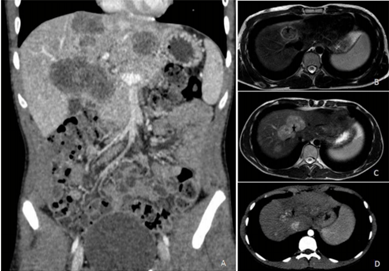

Paciente de 45 anos, sexo masculino, conta história de dificuldade de evacuar completamente e necessidade de tentar evacuar quatro a cinco vezes ao dia, em pequena quantidade, sem sangue, muco ou alteração no formato das fezes, há cerca de um mês e meio. Há 10 dias, iniciou dor abdominal difusa em cólica e alguns episódios de vômitos. Perdeu 5 kg no último mês. Refere ser constipado de longa data. Nega doenças prévias. É tabagista ativo (40 anos-maço). Exame físico: estado geral preservado, descorado (++/4), anictérico, afebril. Palpação do abdômen: fígado palpável a 14 cm do rebordo costal direito e 9 cm do rebordo costal esquerdo, endurecido e aparentemente irregular; baço não palpável. Exames laboratoriais: hemoglobina 10,1 g/L; TGO 58 UI/L; TGP 52 UI/L; fosfatase alcalina 287 UI/L, gama GT 274 UI/L; bilirrubina: total 1,4 mg/d; indireta 0,5 mg/dL e direta 0,9mg/d, RNI 1,42. Tomografia computadorizada de abdômen com imagem abaixo.

Em relação a esse paciente, a hipótese diagnóstica e a conduta são, respectivamente: